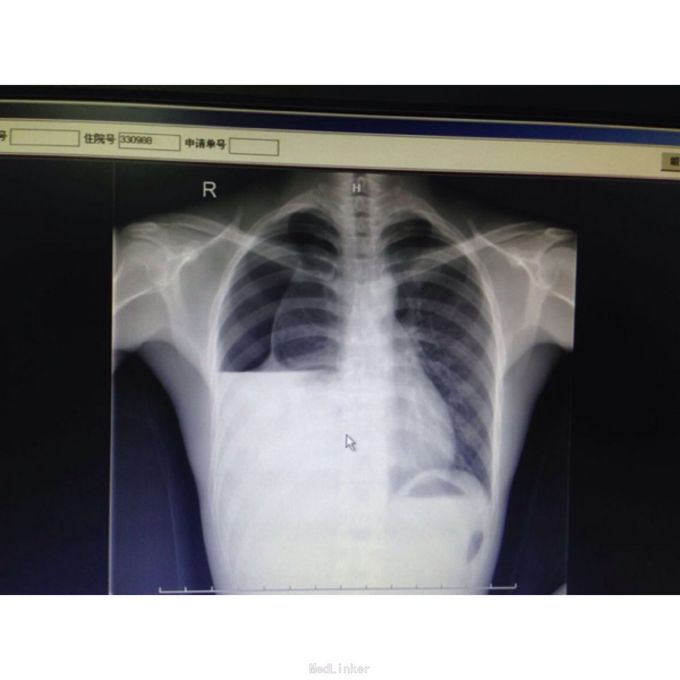

患者男,23岁,因“右胸痛1天”收入本区。患者昨日晚上无明显诱因出现右侧胸痛,深呼吸、咳嗽、转身时加重,无发射性痛,伴气促,活动后明显,休息后可缓解,无发热、头晕、头痛,无咳嗽、咳痰,无心悸,患者为求诊治遂至我院门诊就诊,门诊行胸部正侧位片示“1、右侧液气胸,右肺组织压缩达80%以上右侧胸膜腔次中量积液。2、右中下肺野、右心缘及右膈面被遮挡,建议CT扫描以利观察。”,为求进一步诊治收至我科。

体查:T:37.1℃ R: 21次/分 P:83次/分 BP:125/68mmHg,发育正常,高瘦体型,自主体位,步态平稳,表情自如,神志清楚,对答切题,查体合作。皮肤粘膜未见苍白、黄染,未见皮疹,无皮下出血点,无伤口。全身浅表淋巴结未扪及肿大。颈软,无抵抗,颈静脉无充盈,肝颈静脉回流征(-),气管居中,胸廓对称无畸形、无局部膨隆或凹陷。呼吸稍促,节律规则。右侧呼吸动度减弱。左肺叩诊清音,右肺叩诊浊音。左肺呼吸音清,右肺呼吸音减弱,未闻及干湿性啰音。心界不大,心率83次/分,律齐,各瓣膜区未闻及病理性杂音。 辅助检查:胸片:1、右侧液气胸,右肺组织压缩达80%以上右侧胸膜腔次中量积液。2、右中下肺野、右心缘及右膈面被遮挡,建议CT扫描以利观察。

诊断: 右侧自发性气胸伴积液 右肺压缩80% 治疗:入院后在右侧第三肋间与腋前线处行右侧胸腔闭式引流术,术后予吸氧抗炎化痰对症支持治疗,但随后引流管见水柱波动,无气泡逸出,复查胸透:右肺压缩75%。考虑右侧胸腔引流管被复张右肺堵塞。遂在右侧第二肋间锁骨中线外1cm再放置一条引流管,第三天复查双肺CT:1、右侧胸腔闭式引流术后改变,右侧液气胸,右侧胸腔积气较前增多,右肺压缩约60%,右肺感染较前吸收,右肺中下叶肺膨胀不全。2、右肺尖多发肺大泡大致同前。